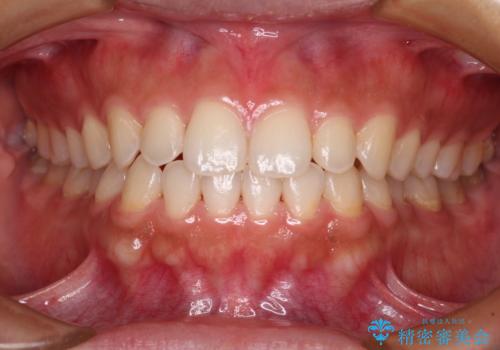

前歯のデコボコをワイヤー矯正できれいに整える

抜歯矯正により口元を引っ込めることも検討しましたが、特に口元の突出感は気になっていないとのことで、非抜歯にてワイヤー装置で矯正治療を行うこととしました。

舌の突出癖により治療期間中に開咬となり、治療が長引きましたが、口元も治療前よりも引っ込めることができ、すっきりとした仕上がりとなりました。